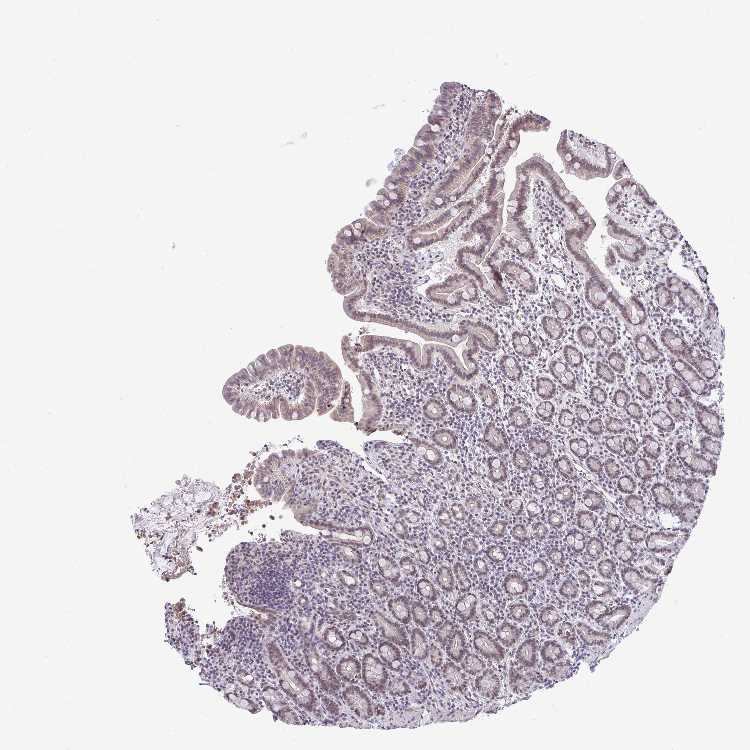

TISSUE PRIMARY DATA SMALL INTESTINE Show tissue menu

SMALL INTESTINE - Antibody stainingi

Antibody staining in the annotated cell types in the current human tissue is reported as not detected, low, medium, or high, based on conventional immunohistochemistry profiling in selected tissues. This score is based on the combination of the staining intensity and fraction of stained cells.

Each image is clickable and will lead to virtual microscopy that enables deeper exploration of all samples and also displays staining intensity scores, fraction scores and subcellular localization as well as patient and tissue information for each sample.

Antibody HPA039242Antibody CAB032896

Glandular cells MediumMedium